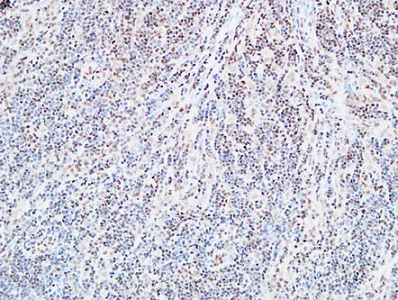

FOXP1 Rabbit Polyclonal Antibody

Cat: APRab11113

Size1:50μl Price1:$118

Size2:100μl Price2:$220

Size3:500μl Price3:$980

Size2:100μl Price2:$220

Size3:500μl Price3:$980